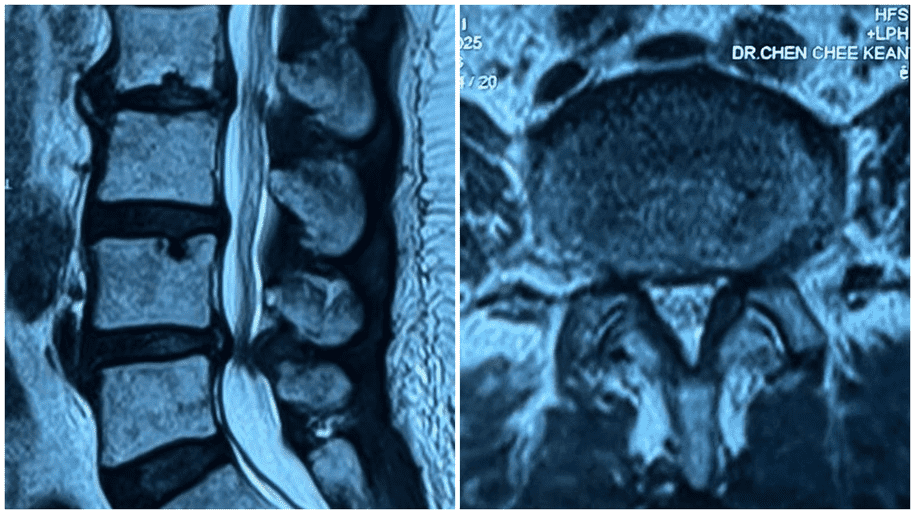

These methods are performed under imaging guidance like X-ray or ultrasound to ensure accuracy and safety.

“For example, if a slipped disc is pressing on a nerve, interventional pain treatment can target that nerve to reduce the pain signal sent to the brain,” Dr Chen explained.

Like any medical procedure, there are potential risks, including infection, bleeding, numbness, tissue injury, or allergic reactions to injections. Still, Dr Chen emphasised that these risks are low when the procedure is done by a trained doctor in a controlled hospital environment.

“The technique used and the location of treatment will determine the type of side effects, but overall, it’s a very safe procedure,” he said.